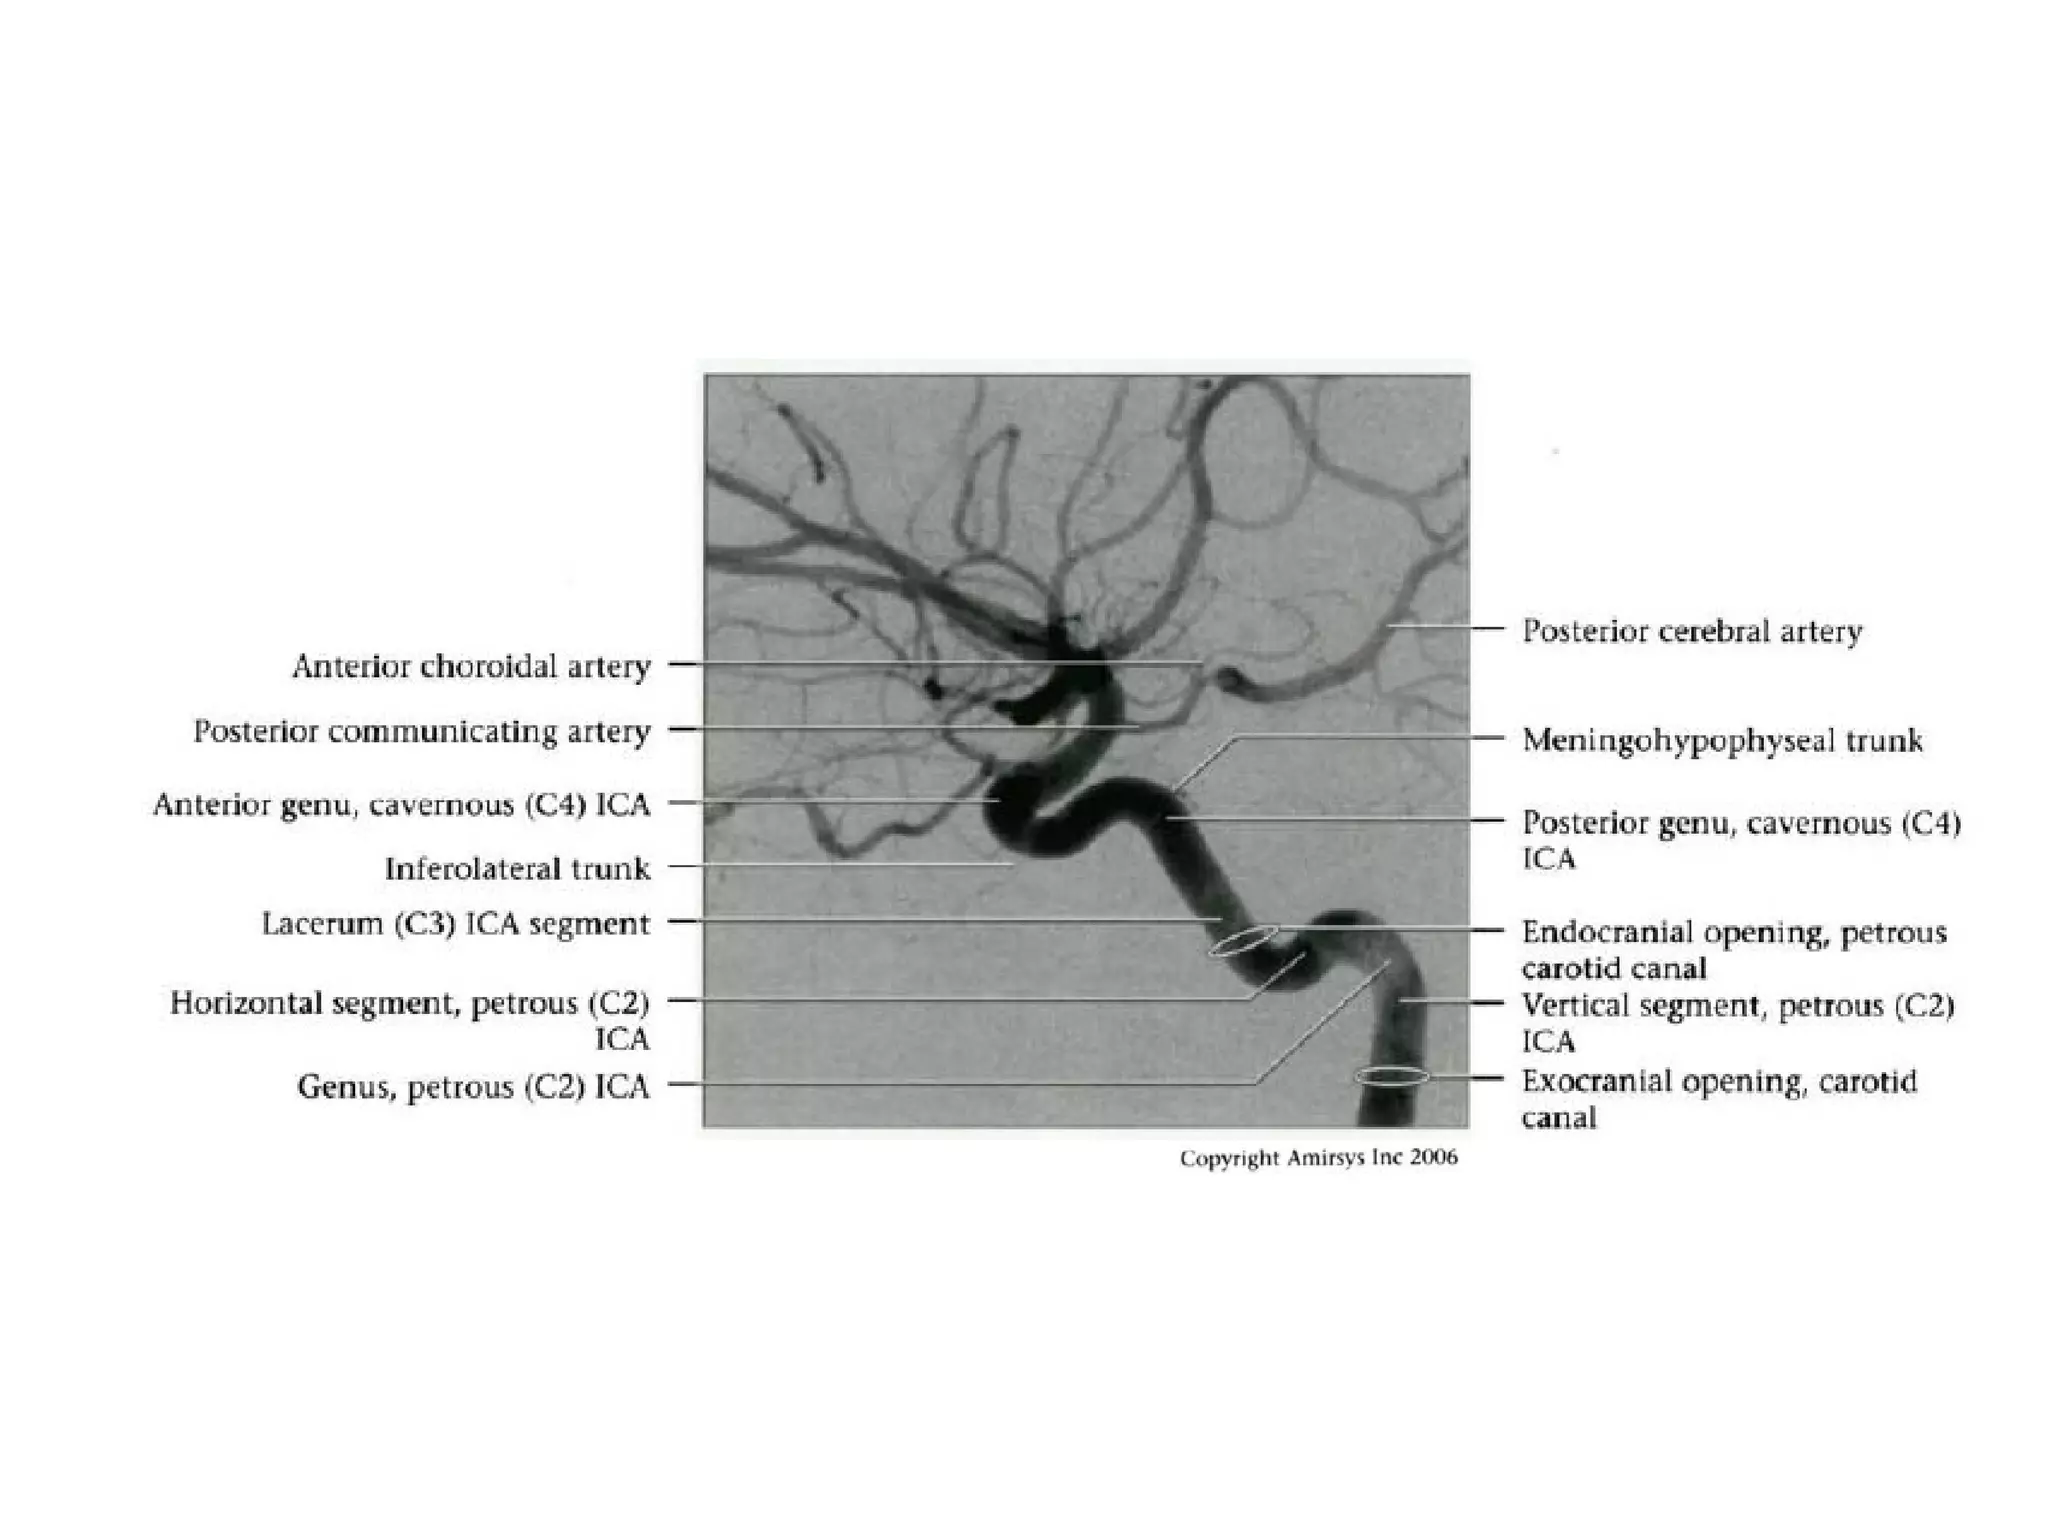

INTRACRANIAL INTERNAL

CAROTID ARTERY

Overview

• Complex course with several vertical /

horizontal segments, 3 genus (one

petrous, two cavernous)

• Six intracranial segments (Cervical lCA =

C1):

- Petrous (C2), Lacerum (C3),

Cavernous (C4), Clinoid (C5),

Ophthalmic (C6), Communicating (C7)

Petrous (C2) segment

• Contained within carotid canal of temporal bone

- Surrounded by extensive sympathetic plexus

- Two C2 subsegments joined at genu

• Short vertical segment - anterior to internal jugular vein

(lJV)

• "Genu" (where petrous ICA turns anteromedially in front

of cochlea)

• Longer horizontal segment

- Exits carotid canal at petrous apex

- Branches

• Vidian artery (artery of pterygoid canal)

anastomoses with external carotid artery (ECA)

• Caroticotympanic artery (supplies middle ear)

Lacerum (C3) segment

• Small segment that extends from petrous

apex above foramen lacerum, curving

upwards toward cavernous sinus

• Covered by trigeminal ganglion

• No branches

Cavernous (C4) segment

• Three subsegments joined by two genus (knees)

- Posterior vertical (ascending) portion

- Posterior (more medial) genu

- Horizontal segment

- Anterior (more lateral) genu

- Anterior vertical (subclinoid) segment

• Covered by trigeminal ganglion posteriorly

• Abducens nerve (CN6) is inferolateral

• Major branches

- Meningohypophyseal trunk (arises from posterior

genu, supplies pituitary, tentorium and clival dura)

- Inferolateral trunk arises from horizontal segment,

supplies cavernous sinus (CS) dura / cranial nerves;

anastomoses with ECA branches through foramens

rotundum, spinosum, ovale